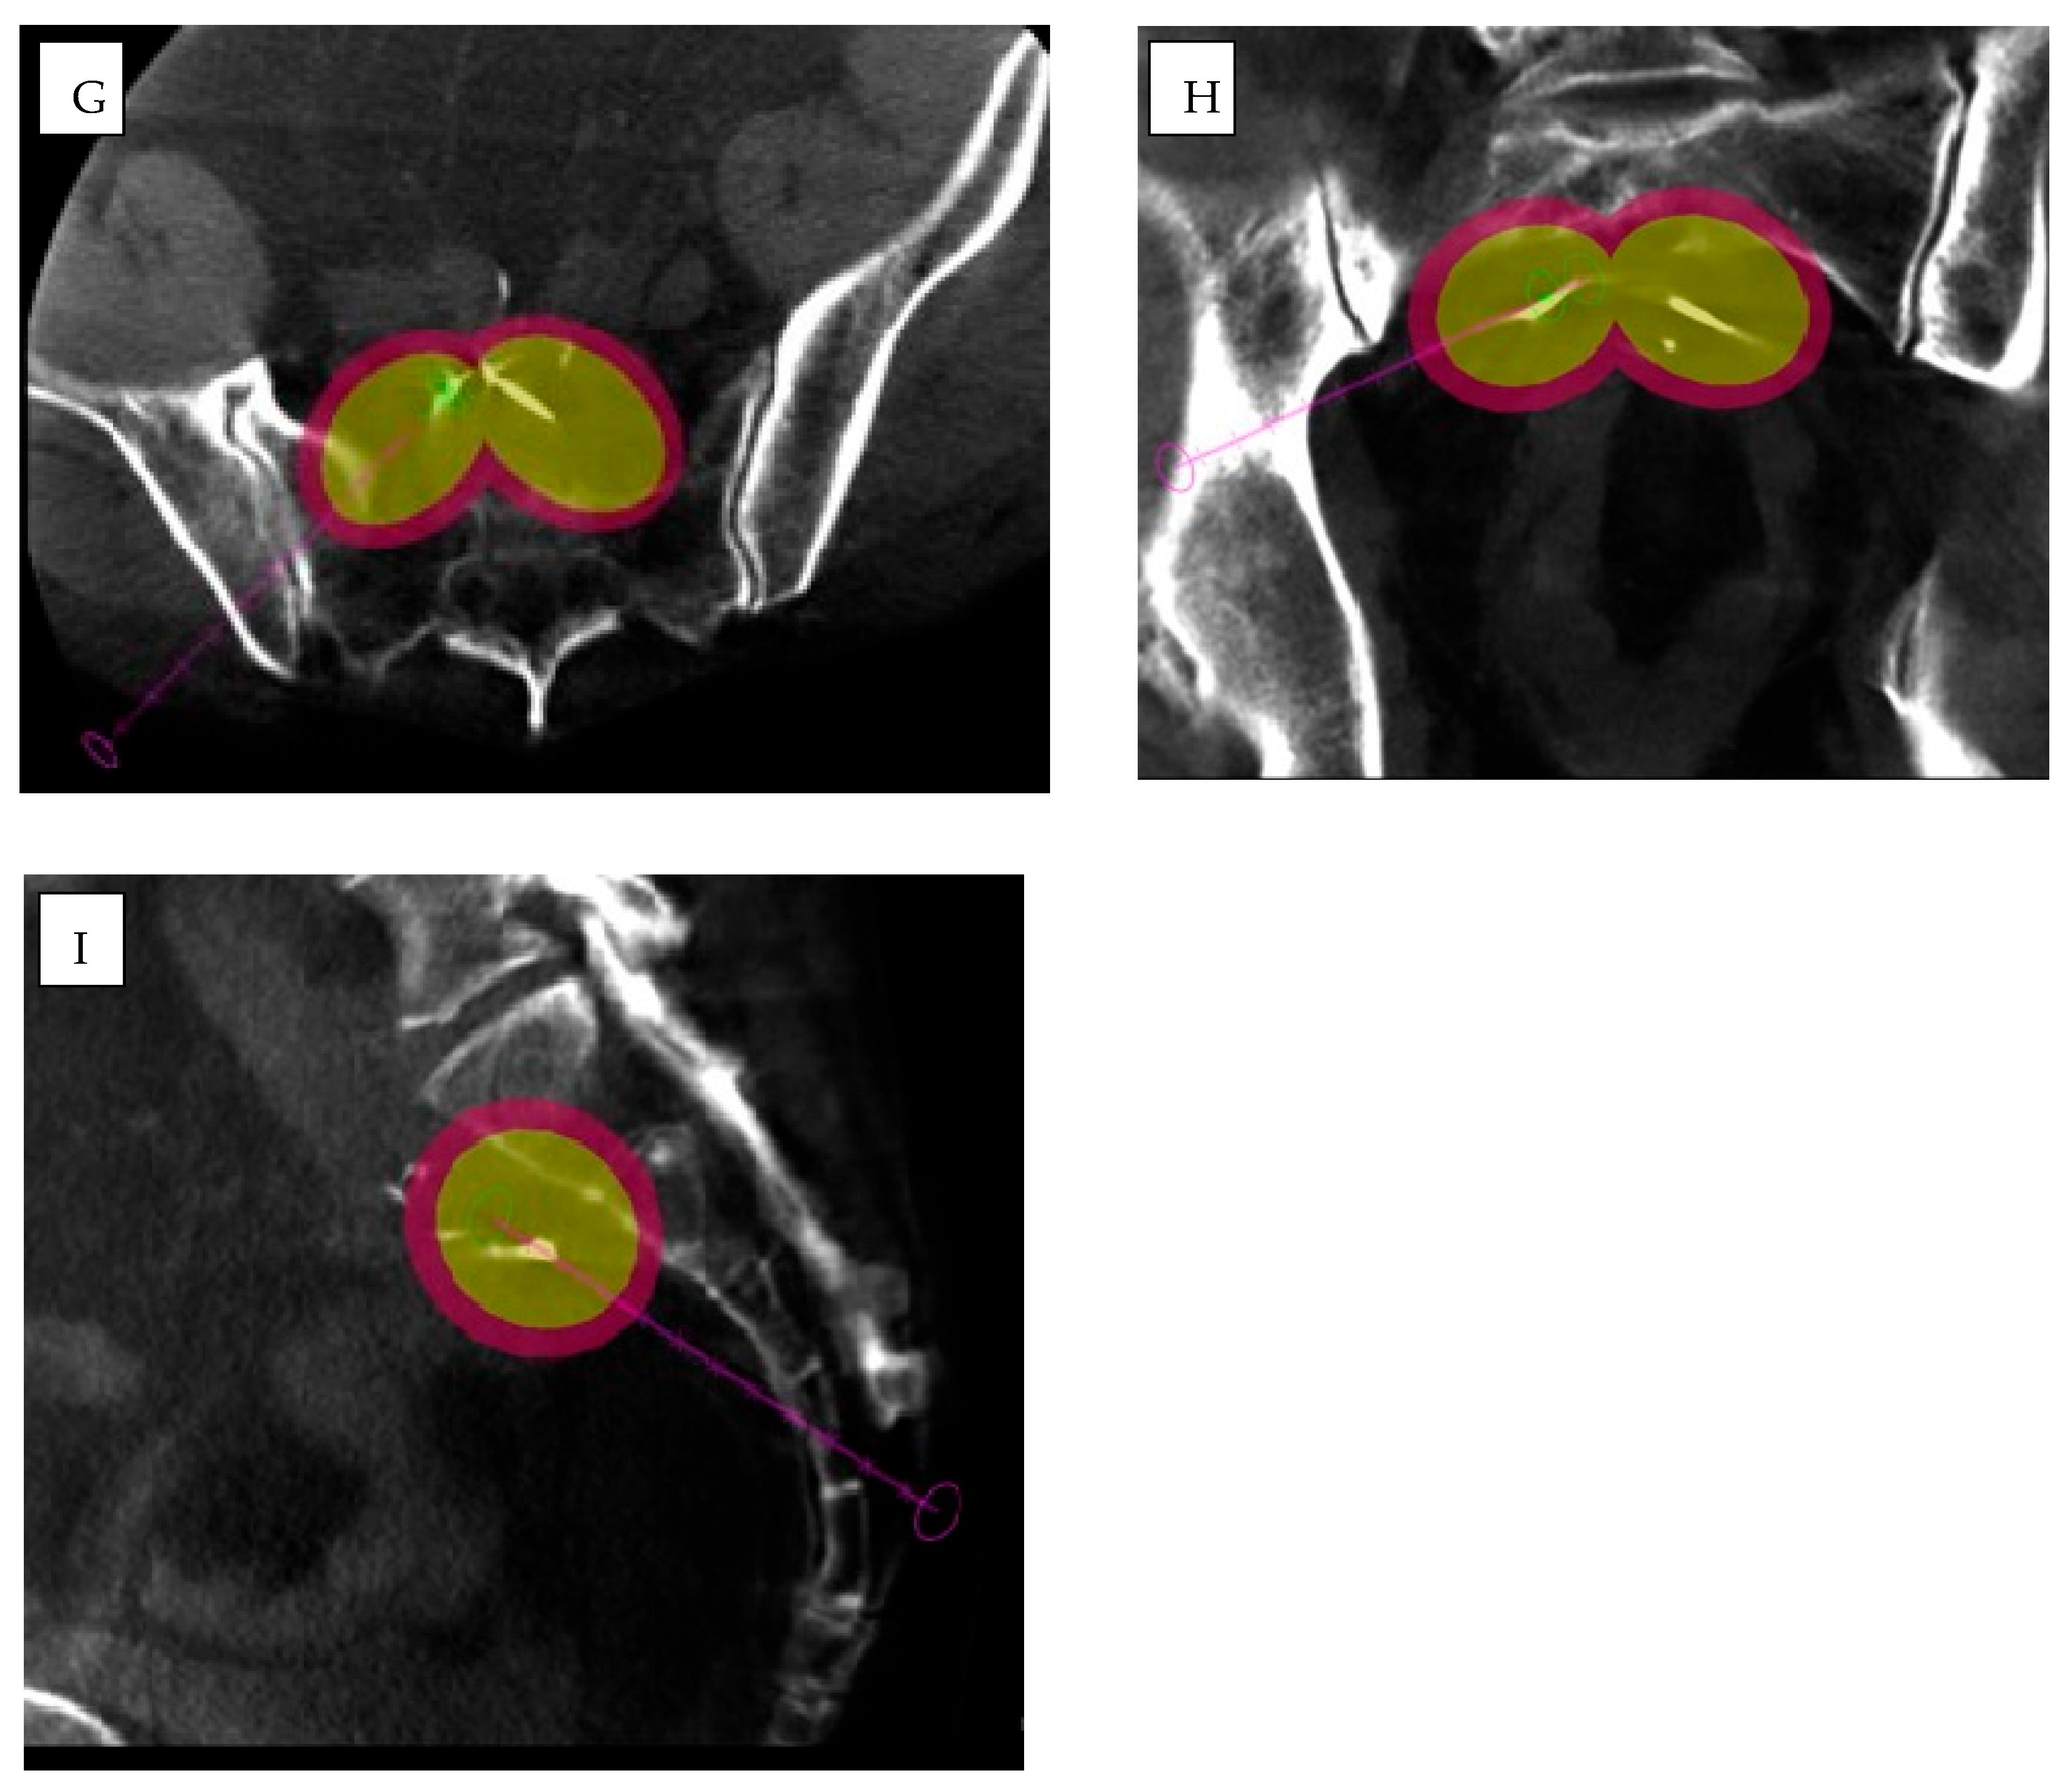

- Qin, S.; Liu, K.; Chen, Y.; Zhou, Y.; Zhao, W.; Yan, R.; Xin, P.; Zhu, Y.; Wang, H.; Lang, N. Prediction of pathological response and lymph node metastasis after neoadjuvant therapy in rectal cancer through tumor and mesorectal MRI radiomic features. Sci. Rep. 2024, 14, 21927. [Google Scholar] [CrossRef] [PubMed]

- Liu, C.; Zhao, W.; Xie, J.; Lin, H.; Hu, X.; Li, C.; Shang, Y.; Wang, Y.; Jiang, Y.; Ding, M.; et al. Development and validation of a radiomics-based nomogram for predicting a major pathological response to neoadjuvant immunochemotherapy for patients with potentially resectable non-small cell lung cancer. Front. Immunol. 2023, 14, 1115291. [Google Scholar] [CrossRef]

- Buijs, E.; Maggioni, E.; Mazziotta, F.; Lega, F.; Carrafiello, G. Clinical impact of AI in radiology department management: A systematic review. Radiol. Med. 2024, 129, 1656–1666. [Google Scholar] [CrossRef]

- Chehab, M.A.; Brinjikji, W.; Copelan, A.; Venkatesan, A.M. Navigational Tools for Interventional Radiology and Interventional Oncology Applications. Semin. Interv. Radiol. 2015, 32, 416–427. [Google Scholar] [CrossRef]

- Chehab, M.; Kouri, B.E.; Miller, M.J.; Venkatesan, A.M. Image Fusion Technology in Interventional Radiology. Tech. Vasc. Interv. Radiol. 2023, 26, 100915. [Google Scholar] [CrossRef]

| Percutaneous applications | Barral et al. [10] | Robotic actuation and image-guided navigation | CT, MRI, US | Biopsy, prostate | Improves targeting and procedural accuracy. | |